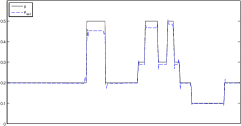

The data (see Figures 1 and 2) was generated in the diffusion model (1.2) using self-written (linear-basis) finite element code in MATLAB. For both examples, we took and used a uniform boundary condition . The simulated data were generated on a -grid and then down-sampled (by averaging) to to avoid inverse crime. After that, Gaussian noise with different intensities (standard deviations of and of the average signal value ) was added to the data.

Reconstruction results and error profiles at different noise levels can be seen in Figures 3 and 4. In both examples, the noise-free reconstructions are very accurate and contain mostly smoothing error. In the low-noise reconstructions, due to the fact that more regularization is necessary, some of the parameter variation is underestimated. In the high-noise examples, most detail in is lost since a lot of regularization is required to get reasonable results. The fine detail in can, however, still be recovered very accurately in both examples.